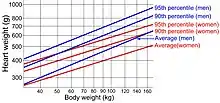

- Autopsy: Cardiomegaly is indicated if the heart weighs more than >399 grams in women and >449 grams in men.[28]